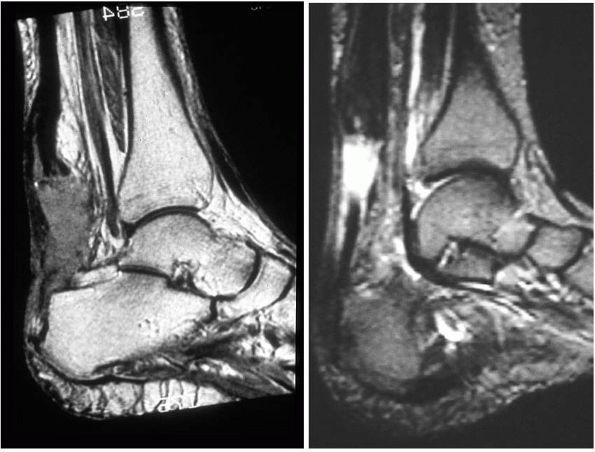

![]() |

FIGURE 21-32. MRI images of Achilles tendinosis demonstrating intrasubstance tendon degenerative change.

tenderness along the tendon in acute disorders. Chronic disorders may

present with more subtle and variable findings; often, nodular swelling

of the tendon may present suggestive of tendinosis (Figure 21-32).